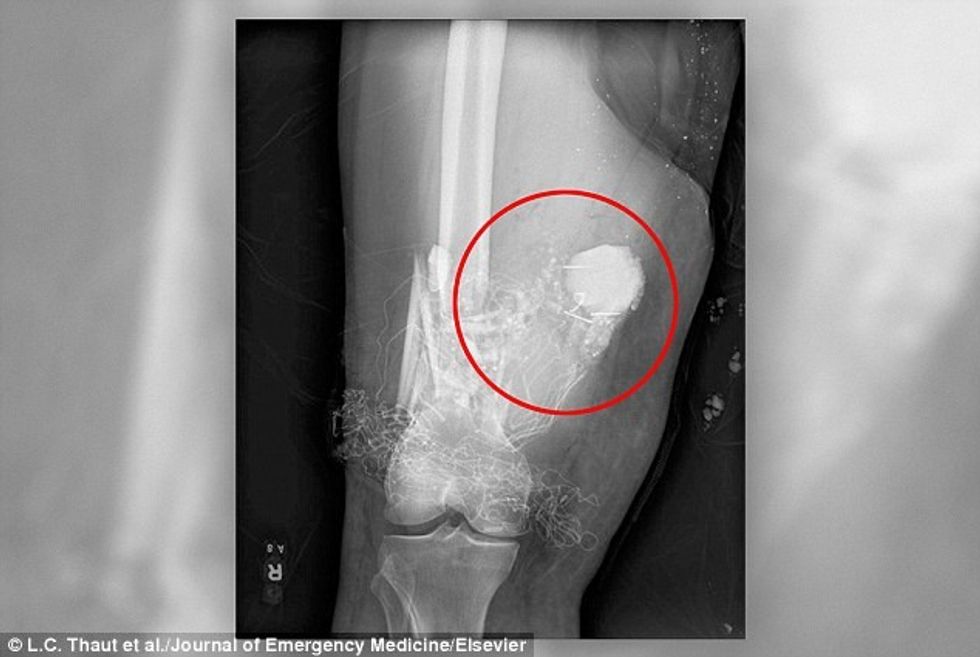

Fotografimi me rreze X, tregonte se mbi gjurin e 44-vjeçari të paidentifikuar ndodhej një mjet plasës, që mund të rrezikonte të gjithë në rast eksplodimi, transmeton Telegrafi.

Kur u siguruan që fishekzjarri nuk do të ndizet, gjatë apo pas nxjerrjes, e caktuan edhe datën e intervenimit. Që gjithçka të shkonte në rregull, shmangën përdorimin e çdo mjeti të nxehtë.

Intervenimi është realizuar nën kontrollin e njohësve të predhave dhe kaloi pa eksplodim. Pacienti që qëndroi për dy javë nën kujdesin mjekësor, është lëshuar në shtëpi. /Telegrafi/